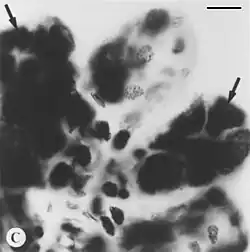

Feulgen stain

Feulgen stain is a staining technique discovered by Robert Feulgen and used in histology to identify chromosomal material or DNA in cell specimens. It is darkly stained. It depends on acid hydrolysis of DNA, therefore fixating agents using strong acids should be avoided.[1]

DNA should be stained red.[1] The background, if counterstained, is green. This reaction is also specific to DNA since RNA is characterized by a ribose sugar, instead of deoxyribose, preventing acid hydrolysis. This impedes purine detachment and thus do not allow the staining.[1]